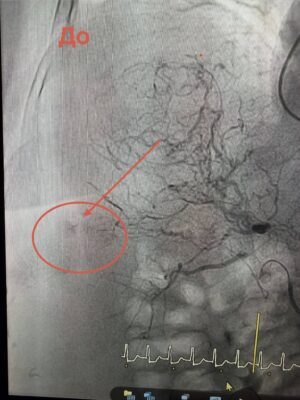

Через загрозливий стан проводити відкриту операцію було неможливо. Натомість лікарі застосували метод ендоваскулярної хірургії — за допомогою ангіографії визначили джерело кровотечі та виконали емболізацію судини, що дозволило її зупинити без масштабного хірургічного втручання.